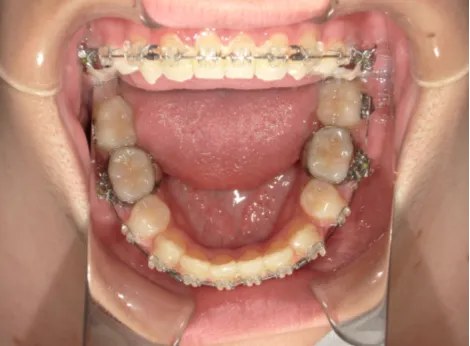

治療中⑧高1:15y11m 抜歯治療中

治療中⑨高2:17y1m 抜歯治療中

治療後⑩高2:17y7m 抜歯治療終了